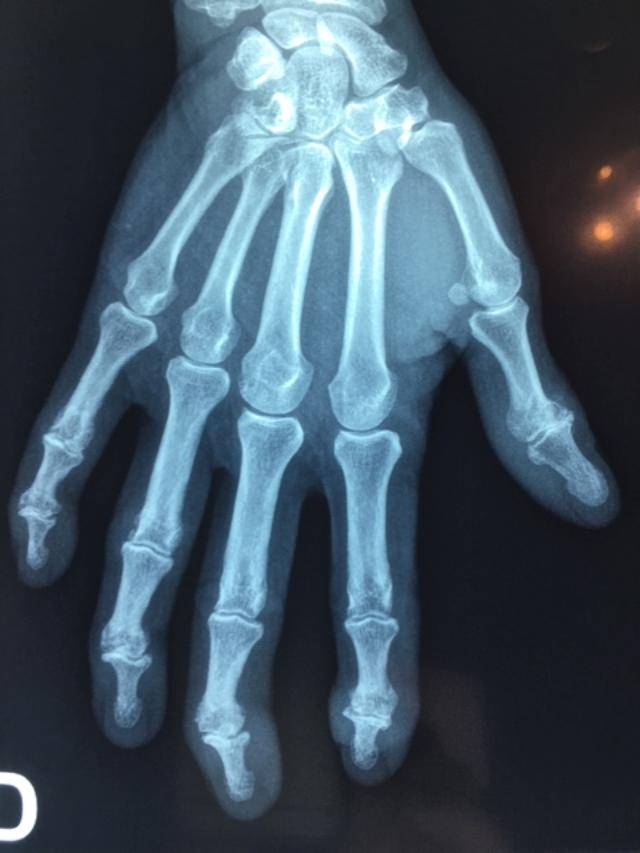

Les déformations des doigts peuvent résulter de plusieurs causes : arthrose, polyarthrite rhumatoïde ou séquelles traumatiques. Ces atteintes provoquent douleurs, gêne fonctionnelle et limitations dans les gestes du quotidien. Dans notre cabinet d’orthopédie sur mesure à Allauch, proche de Saint-Barnabé, nous réalisons des orthèses digitales thermoformées destinées à soulager les articulations et à limiter la progression des déformations.

Arthrose des doigts : une atteinte fréquente et évolutive

L’arthrose digitale touche jusqu’à 35 % des femmes et 25 % des hommes. Il s’agit d’un phénomène d’usure des surfaces articulaires pouvant se manifester :

• au niveau du pouce (rhizarthrose),

• au niveau des articulations interphalangiennes des doigts.

Son évolution est très variable : certains patients restent peu gênés, tandis que d’autres connaissent douleurs intenses, crises inflammatoires et déformations progressivement irréversibles.